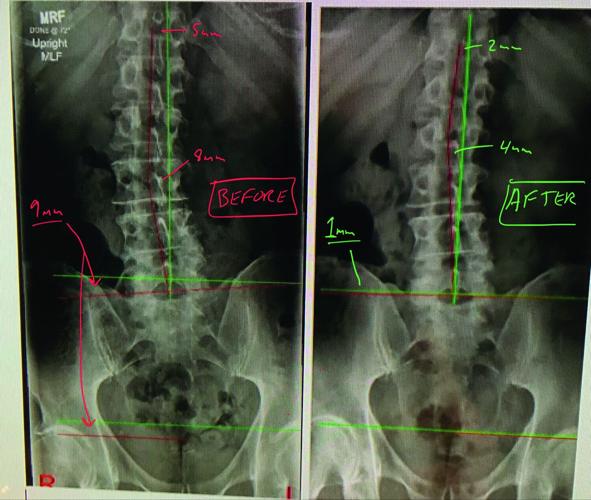

An X-ray shows a right-sided short leg (9 mm shorter than the left leg) and its affect on posture (left) and the improvement (right) that can be seen after intervention brings the difference at the pelvis to 1 mm. (COURTESY IMAGES)